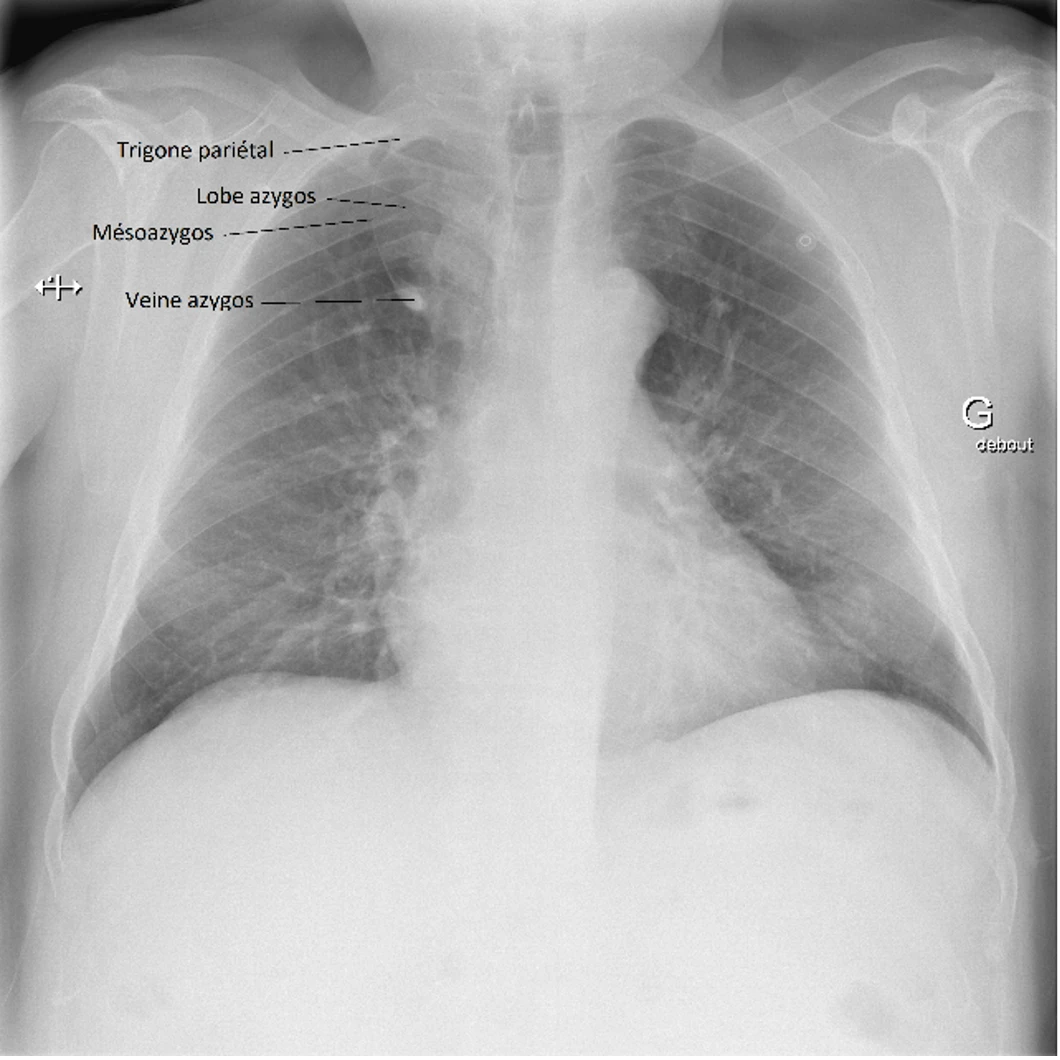

Masse dans le lobe supérieur droit

Le lobe azygos est une anomalie congénitale, ou variante anatomique. Bien que rare (il se retrouve chez environ 1% de la population avec un ratio homme : femme de 2 : 1 et sur 0.4 % des radiographies thoraciques), cette variante doit être connue de la ou du clinicien·ne car elle peut être confondue avec un néoplasie pulmonaire, un abcès ou une bulle d’emphysème voir un pneumothorax.

Les signes radiologiques classiques sont :

1. Au niveau paratrachéal droit :

• Une image de larme par la présence de la veine azygos déplacée latéralement et se retrouvant piégée dans le parenchyme pulmonaire et les plis de la plèvre

• Une image de virgule inversée par la veine qui indente le lobe supérieur droit et crée une scissure accessoire (pli de la plèvre pariétale et viscérale, mésoazygos)

2. À la portion supérieure de la fissure : une opacité triangulaire, le trigone pariétal, qui est du tissu extrapulmonaire pris en sandwich lors de la migration de la veine azygos.

3. Au bord inférieur de la bande paratrachéale droite : le renflement habituellement présent en raison du passage de la veine azygos à l’angle trachéobronchique n’est pas visible.